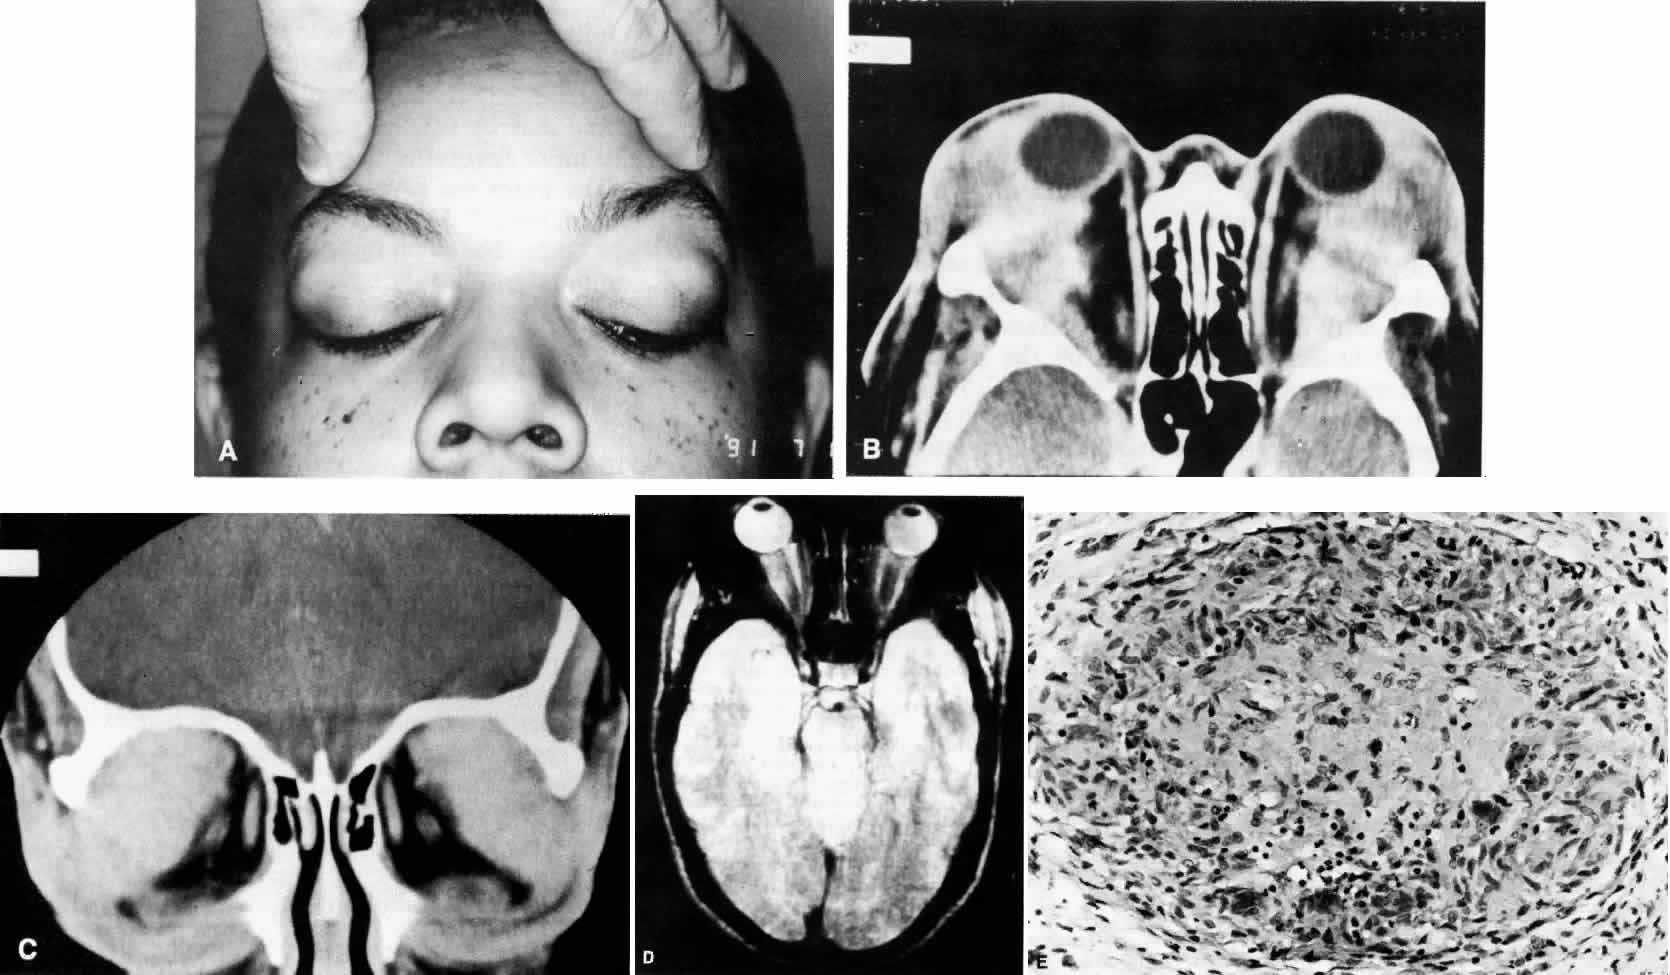

Fig. 11. A. This 31-year-old man has had Wegener's granulomatosis for 2 years. His disease process is stable on chronic corticosteroid therapy. He has no evidence of systemic disease. Note right-sided proptosis and hyperglobus. B. Profile of same patient demonstrating collapse of nasal bridge from bony destruction secondary to Wegener's granulomatosis. Note presence of swelling in lower eyelid. C. Axial CT image from the same patient demonstrating significant bilateral disease and bony destruction. Despite the extent of the orbital process on the right, the patient does not have diplopia. D. Coronal CT image showing destruction of medial orbital walls, vomer, and orbital septum. E. Pulmonary biopsy specimen from patient with orbital signs contains an almost obliterated vessel to right of center and scattered giant cells on left (H&E, ×160).

Wegener's granulomatosis is characterized by inflammatory lesions of the upper respiratory tract, lower respiratory tract, the kidneys, and, to varying degrees, generalized small vasculitis of other structures, including the eye (Figs. 10 AND 11). The definitive diagnosis is confirmed by biopsy. A limited form of the disease has been described that spares the kidneys.

Ocular manifestations include orbital inflammation, scleritis, keratitis, and uveitis. The ocular involvement can occur from extension of sinus and nasal lesions or from focal small vessel vasculitis.